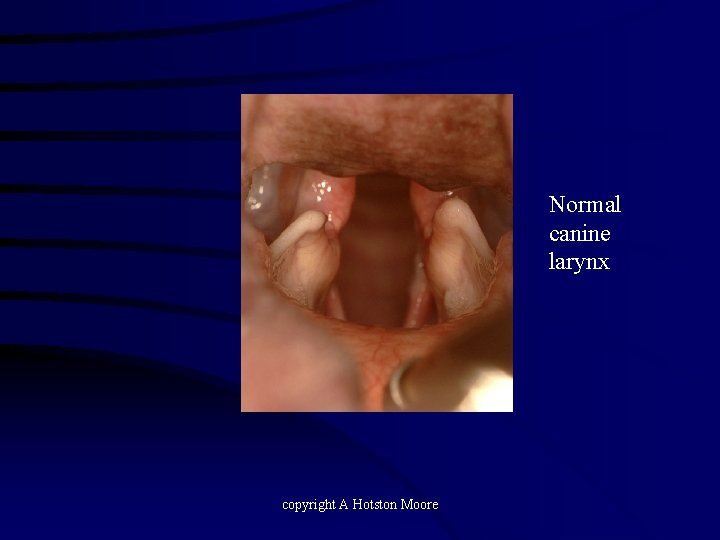

Normal canine larynx copyright A Hotston Moore